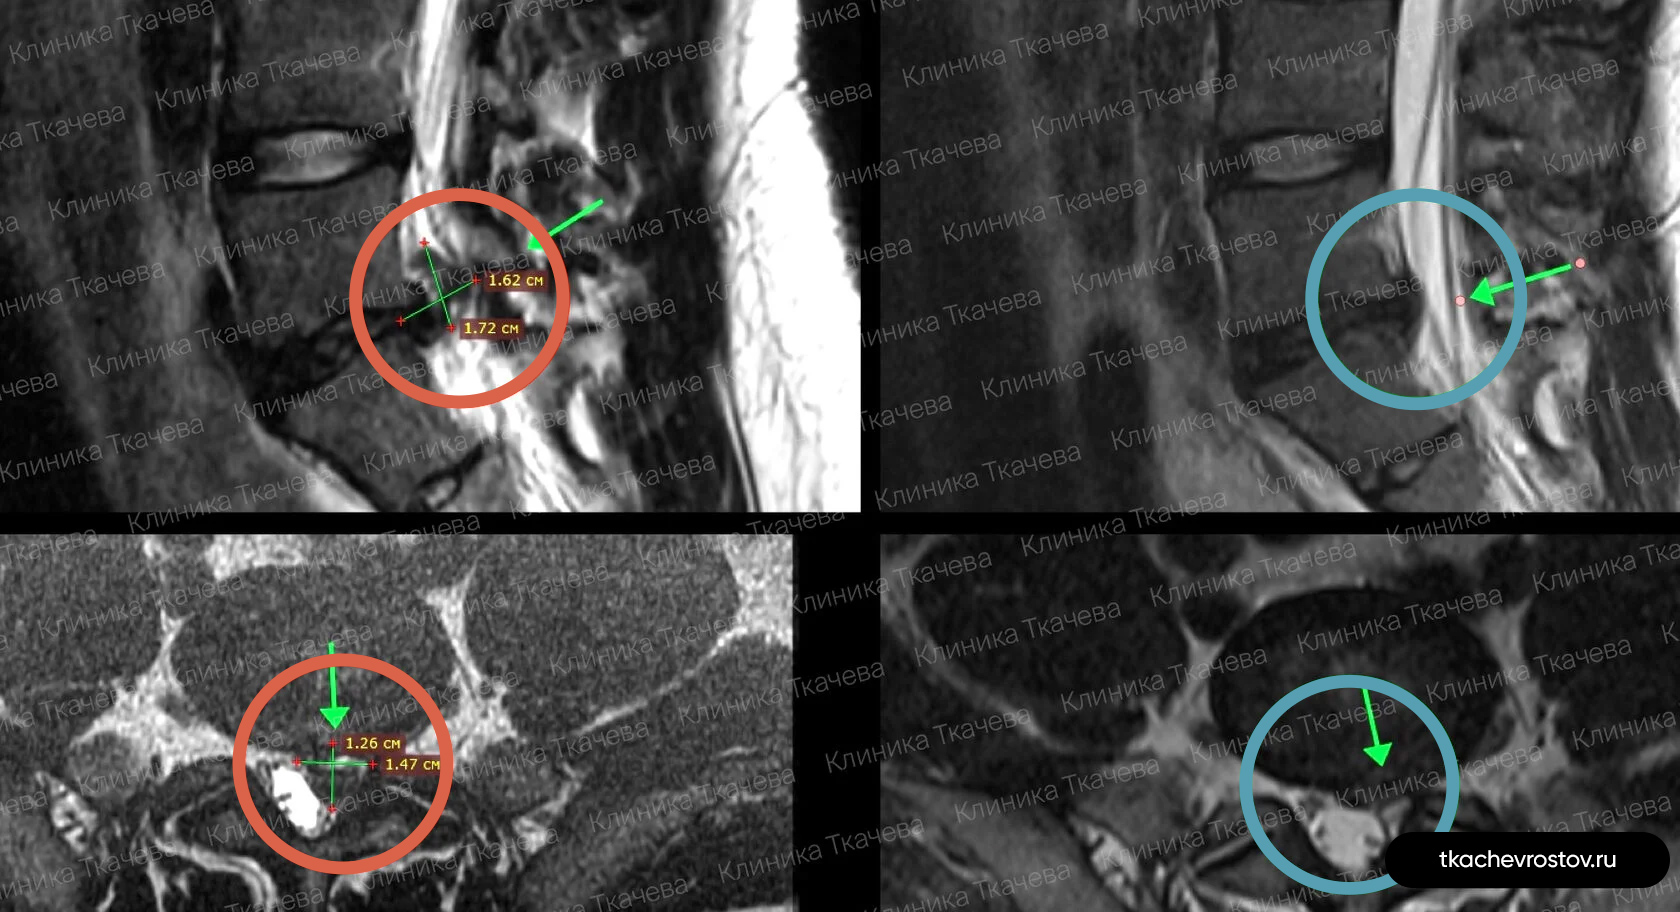

Грыжа в шейном отделе C6-C7

Женщина. Грыжа в шейном отделе C6-C7 1.8х0.8см. Из-за боли передвигалась по стеночке. Отказалась от операции по квоте – замена диска на имплант.

ДО:

- Больно дышать и говорить

- Какие-либо движения головы приносили жуткую боль

- Правая рука не слушалась, частично онемели ладонь и пальцы руки

- Обезболивающие, блокады, капельницы. Ничего не помогло

- Потеря трудоспособности и ограничение жизнедеятельности

ПОСЛЕ 1 курса:

✓ Наступила резорбция грыжи

✓ Наступило улучшения общего состояния

✓ Стала лучше работать правая рука

✓ Ушло частичное онемение

✓ Голова стала поворачиваться во все стороны

✓ Ушла выраженная боль и напряжение в шее

✓ Пациентка смогла сесть за руль

ПОСЛЕ 2 курса:

✓ Полная резорбция грыжи

✓ Восстановление всех двигательных функций

✓ Прекрасное самочувствие

Всё лечение заняло полгода (2 курса по 15 дней).